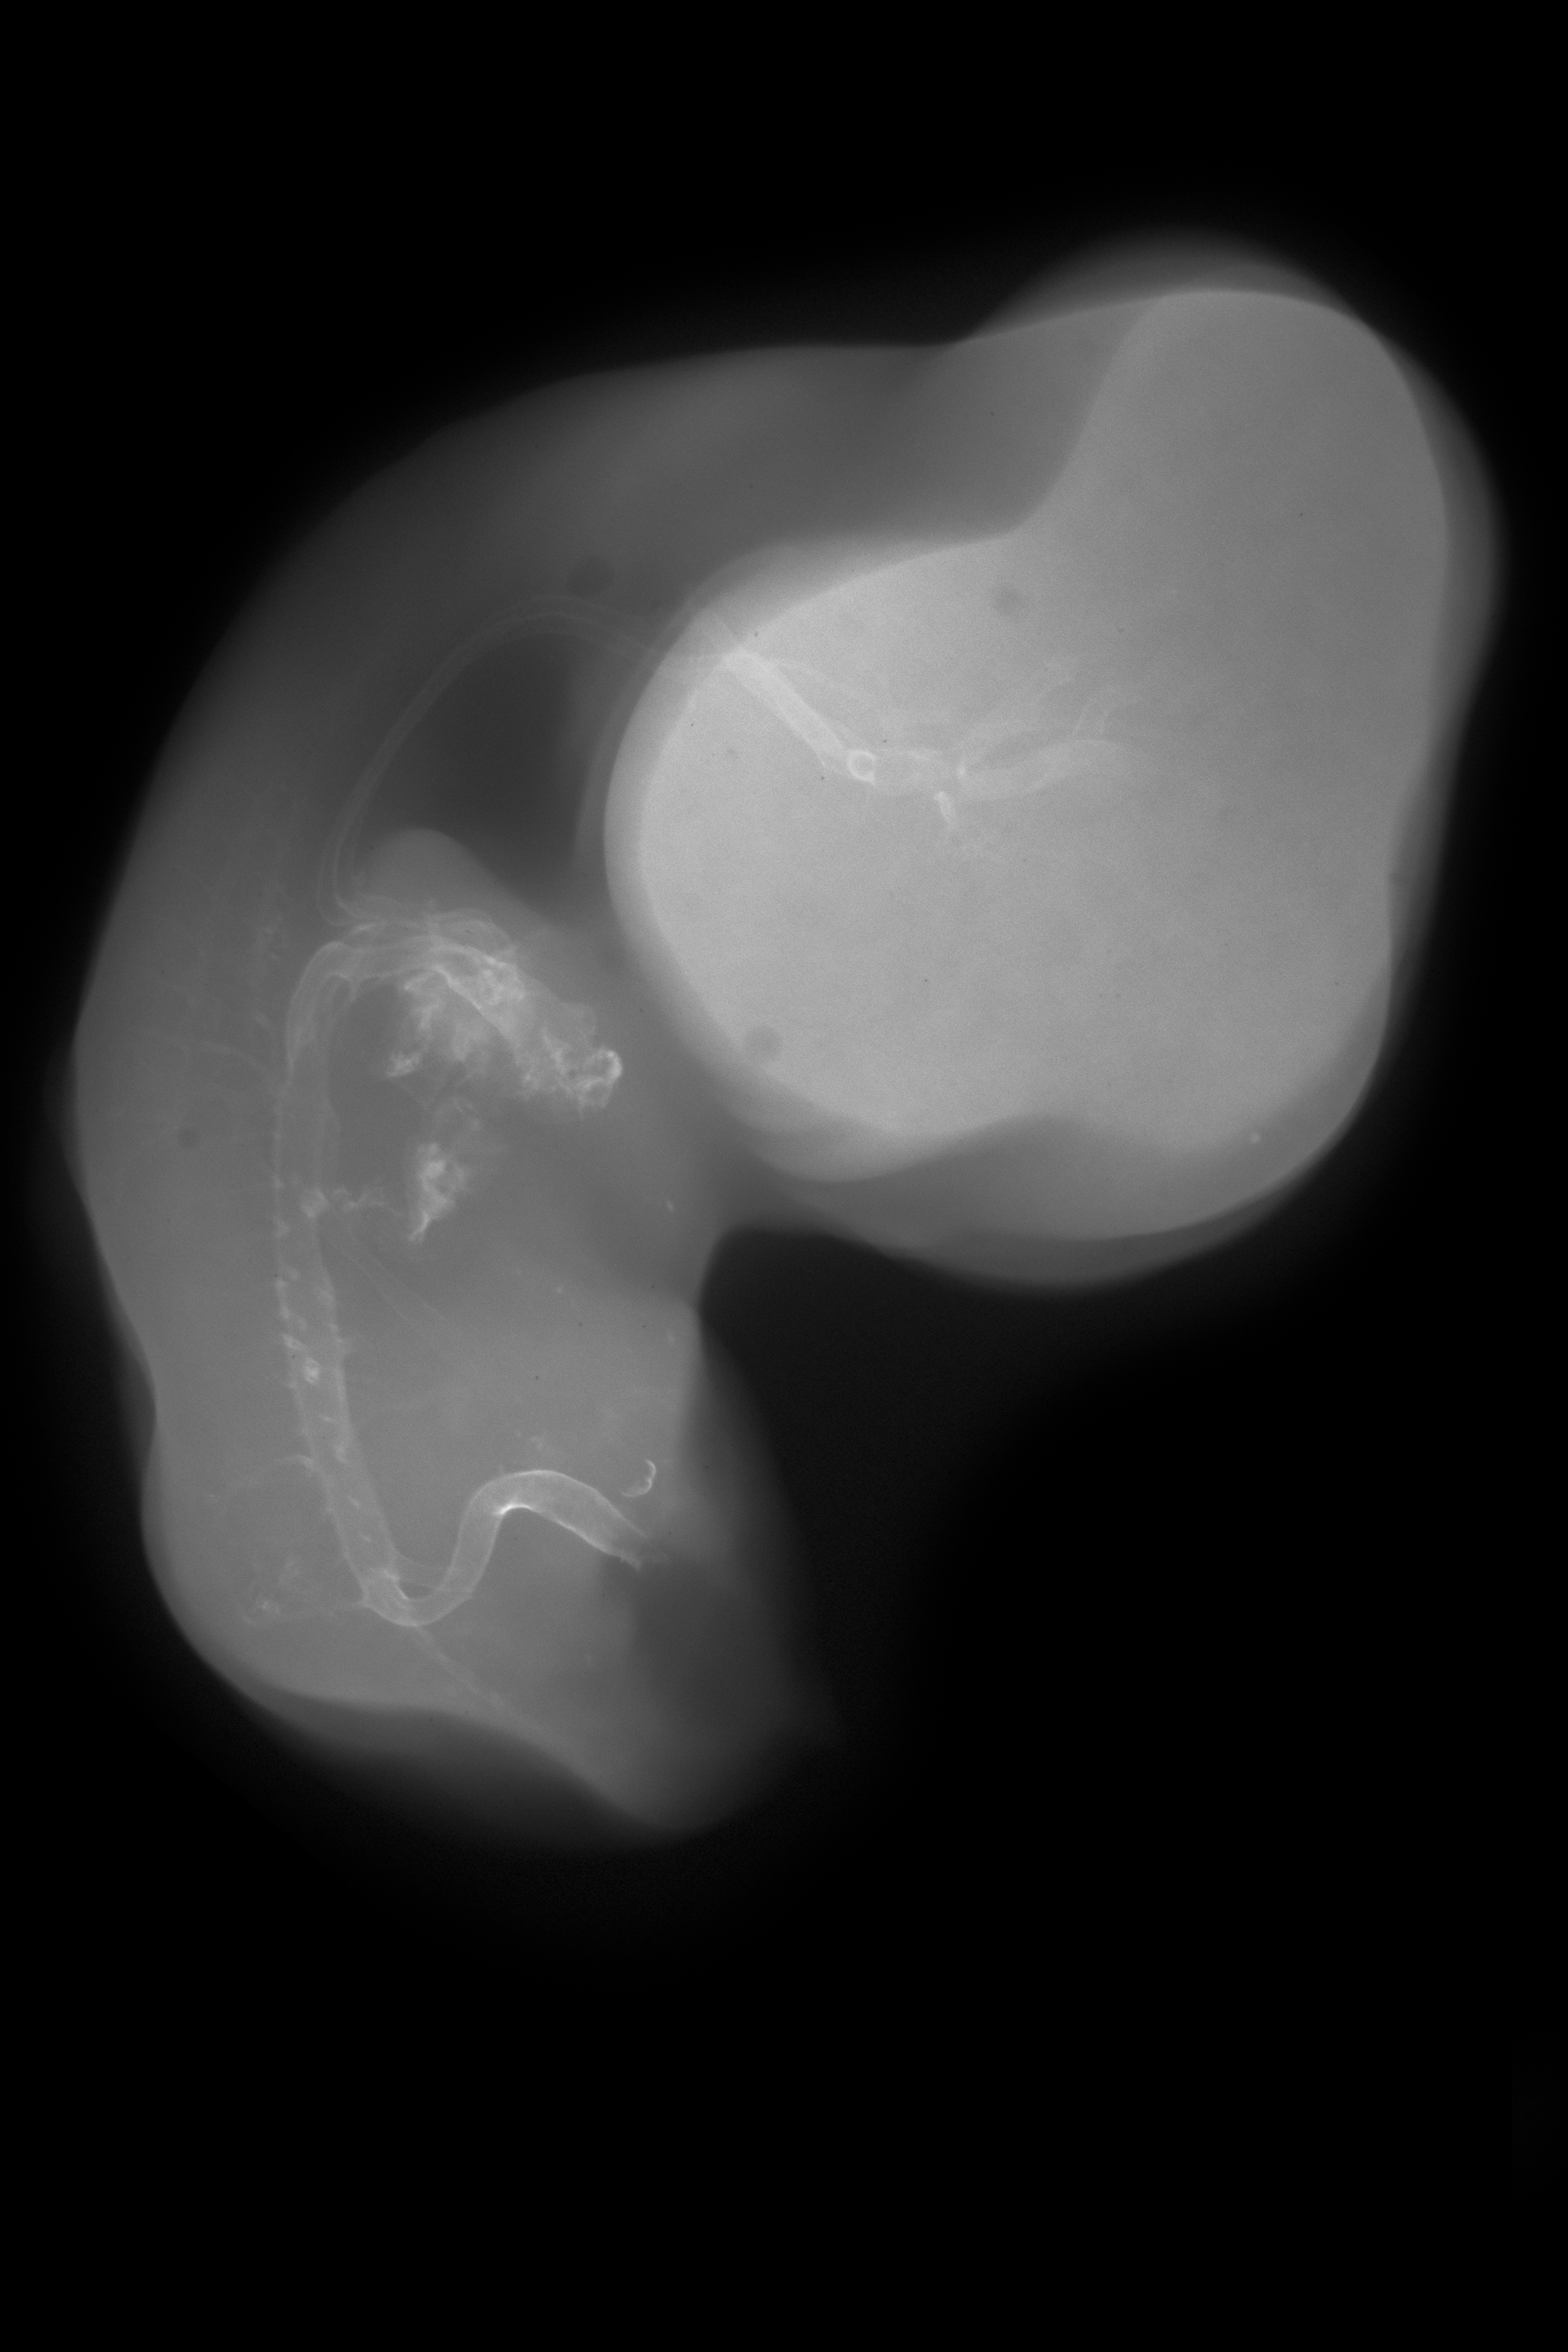

Chick Embryo Microangiography

Hamburger-Hamilton (HH) Stage 29 (approx. 6 - 6.5 days)

Stereo X-Ray Micrographs